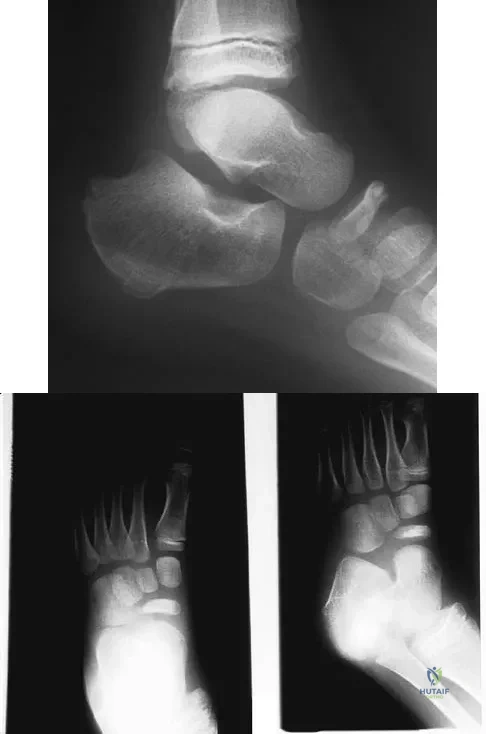

Question 56

A 5-year-old boy has had midfoot pain with activity for the past 3 months. He has no pain at rest. Radiographs are shown in Figures 29a and 29b. Management should consist of

Explanation